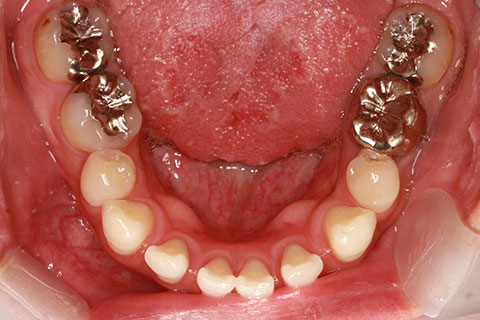

フルリンガル矯正2(上下の歯を舌側矯正で治療)

治療前

治療中

治療後

- 年齢・性別

- 42歳男性

- 治療期間

- 1年6ヶ月

- 抜歯

- なし

- 治療費

- 120万円(税込み)

- 備考

- マルチブラケットを用いた矯正治療

- 治療内容

- 反対咬合をフルリンガル矯正治療にて改善

- 施術の副作用(リスク)

- 表側矯正と比較して、歯根の角度を確立する「トルク」の力がかかりにくい。